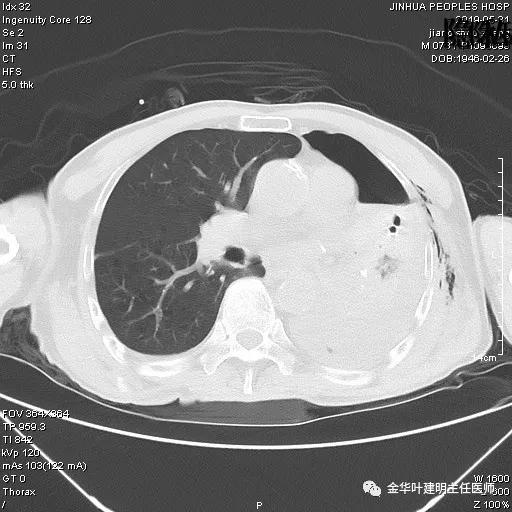

考虑左侧大量胸腔积液,遂进一步胸部CT检查:

以上是肺窗表现,下面为纵隔窗影像: